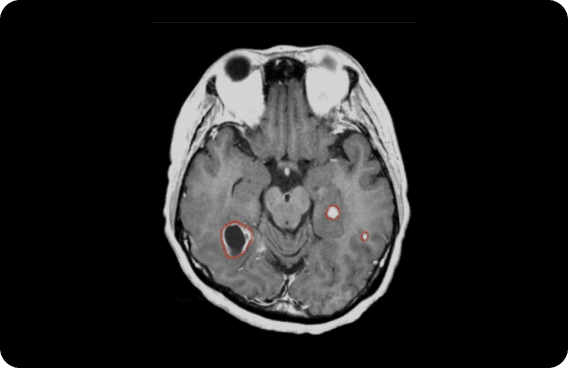

TFDA-Approved AI Model DeepMets®

auto-contouring for tumors

Intelligent assistant specialized in interpreting brain images